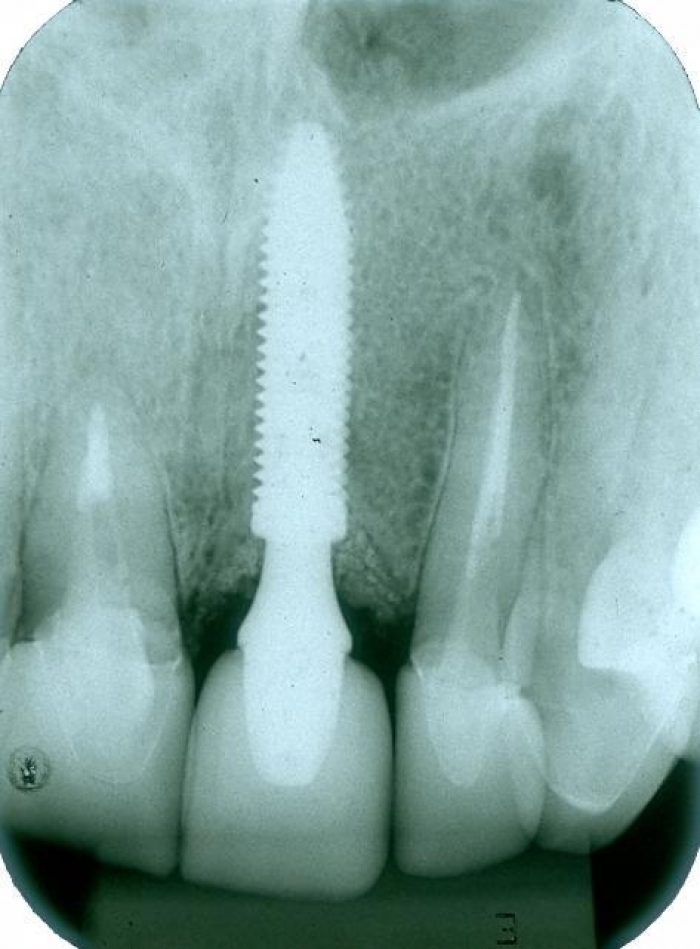

Raio x final